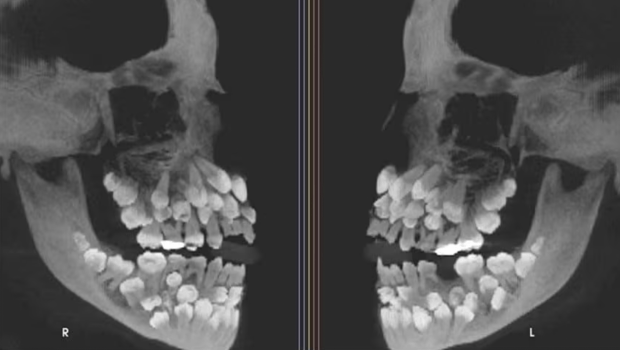

一名11岁的巴西女孩发现,她的嘴里有81颗牙齿,有18个乳牙,32颗恒牙和31颗牙齿的牙齿,成人的牙齿超过正常数量的32颗恒牙。该病例已发表在《美国正畸和牙科骨科杂志》上,该杂志吸引了全球关注的学术关注。 ▲发现一名11岁的巴西女孩的嘴里有81颗牙齿,有18个乳牙,32颗恒牙和31颗牙齿。 《美国牙齿牙和牙科矫形器杂志》证实,全世界很少有罕见的多丹主义案例。这位11岁的女孩去Juisdifola联邦大学牙科医院接受治疗,因为她不得不用落叶牙齿去除上颌。当时,纳图安的临床分析没有明显的异常,但是X射线的结果令人惊讶,因为他宣布他的嘴里有81颗牙齿,最终证实了该女孩具有一级主义。这研究小组进一步使用锥形束计算机断层扫描(CBCT)来确认牙齿的准确位置和形态。他们发现许多牙齿分布在牙齿拱的不同区域,有些牙齿被埋入牙龈深处。形态不是正常的,很难将它们与正常牙齿区分开。多齿在牙齿发育中是一种罕见的异常,通常只有1到2个多牙牙齿,超过30种非常罕见,在全球文献中只有少数病例报告。在这种情况下,31多个牙齿繁琐,患者没有常见的综合征,例如锁骨界异常增生症,加德纳综合征或唇裂和口感,这不是有症状的多伦理,这会增加诊断和治疗挑战。稀有遗传变异的发现预计将被纠正多年。研究小组在遗传专家中提到了该女孩进行审查。 G带分析表明,女孩的外围旋转在9号染色体中,这是一种罕见的遗传变异。但是,研究人员说,目前尚无证据表明旋转直接导致多探测,因为多丹主义的原因尚未完全了解,并且可能涉及板块过度活跃,遗传或环境因素的复杂接触。研究小组教导说,许多牙齿会导致牙刷,永久性牙齿阻塞,偶尔避免咬合或囊肿形成。如果ANG不正确的去除会损坏下颌或相邻的牙齿,则应小心。女孩病例的数量是由于牙齿数量众多,形态异常和复杂分布引起的,这会引起临床问题。直到今天,研究小组一直由一个多学科组组成,包括正畸,口腔和上颌面外科,牙周病和FUFU部门,并起草了长期治疗计划。女孩的治疗预计将持续多年,需要大量操作和更正s。研究小组在报告中说:“十二个多基因牙齿的这种现象显示出差异 - 人类发展的差异。”他们呼吁通过定期牙科检查尽早发现异常。